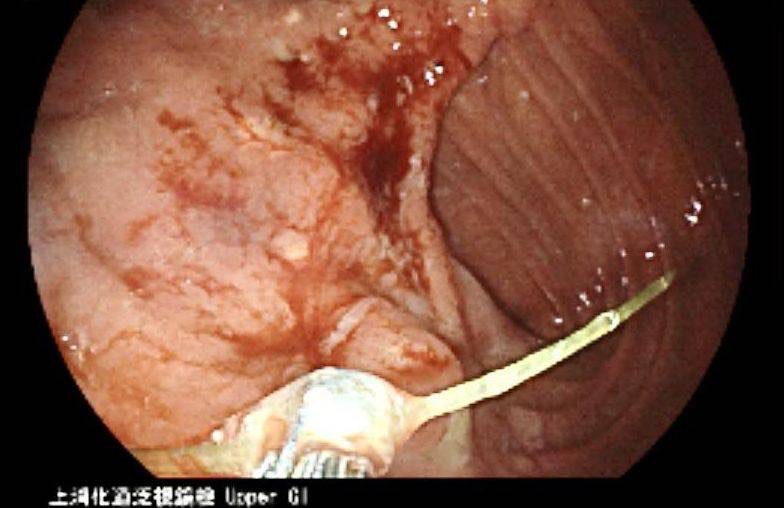

一名60歲男性病患,因腹脹與胃口不佳持續一週,至天主教聖馬爾定醫院求診。病患本身有胃潰瘍與胃部手術病史,原以為是舊疾復發,經腸胃肝膽科羅清池醫師詳細問診與觸診後,懷疑另有原因,立即安排胃鏡檢查,驚見一根約3公分長的魚刺刺入胃壁,已形成局部膿瘍。羅醫師當機立斷,以胃鏡異物鉗成功將魚刺夾出,病人術後迅速恢復進食,症狀也徹底解除。

羅清池醫師指出,該名病患雖無明顯腹痛,但因觸診壓痛與長期食慾不振,讓他懷疑有感染或阻塞,所幸及時安排檢查揪出元凶。若再延誤,魚刺恐導致胃穿孔、腹膜炎甚至敗血症,後果不堪設想。羅醫師機警發現潛藏危機,精準安排檢查並成功移除魚刺,讓病人免於進一步的併發症與手術風險,凸顯他在內視鏡操作的經驗與臨床敏銳度。